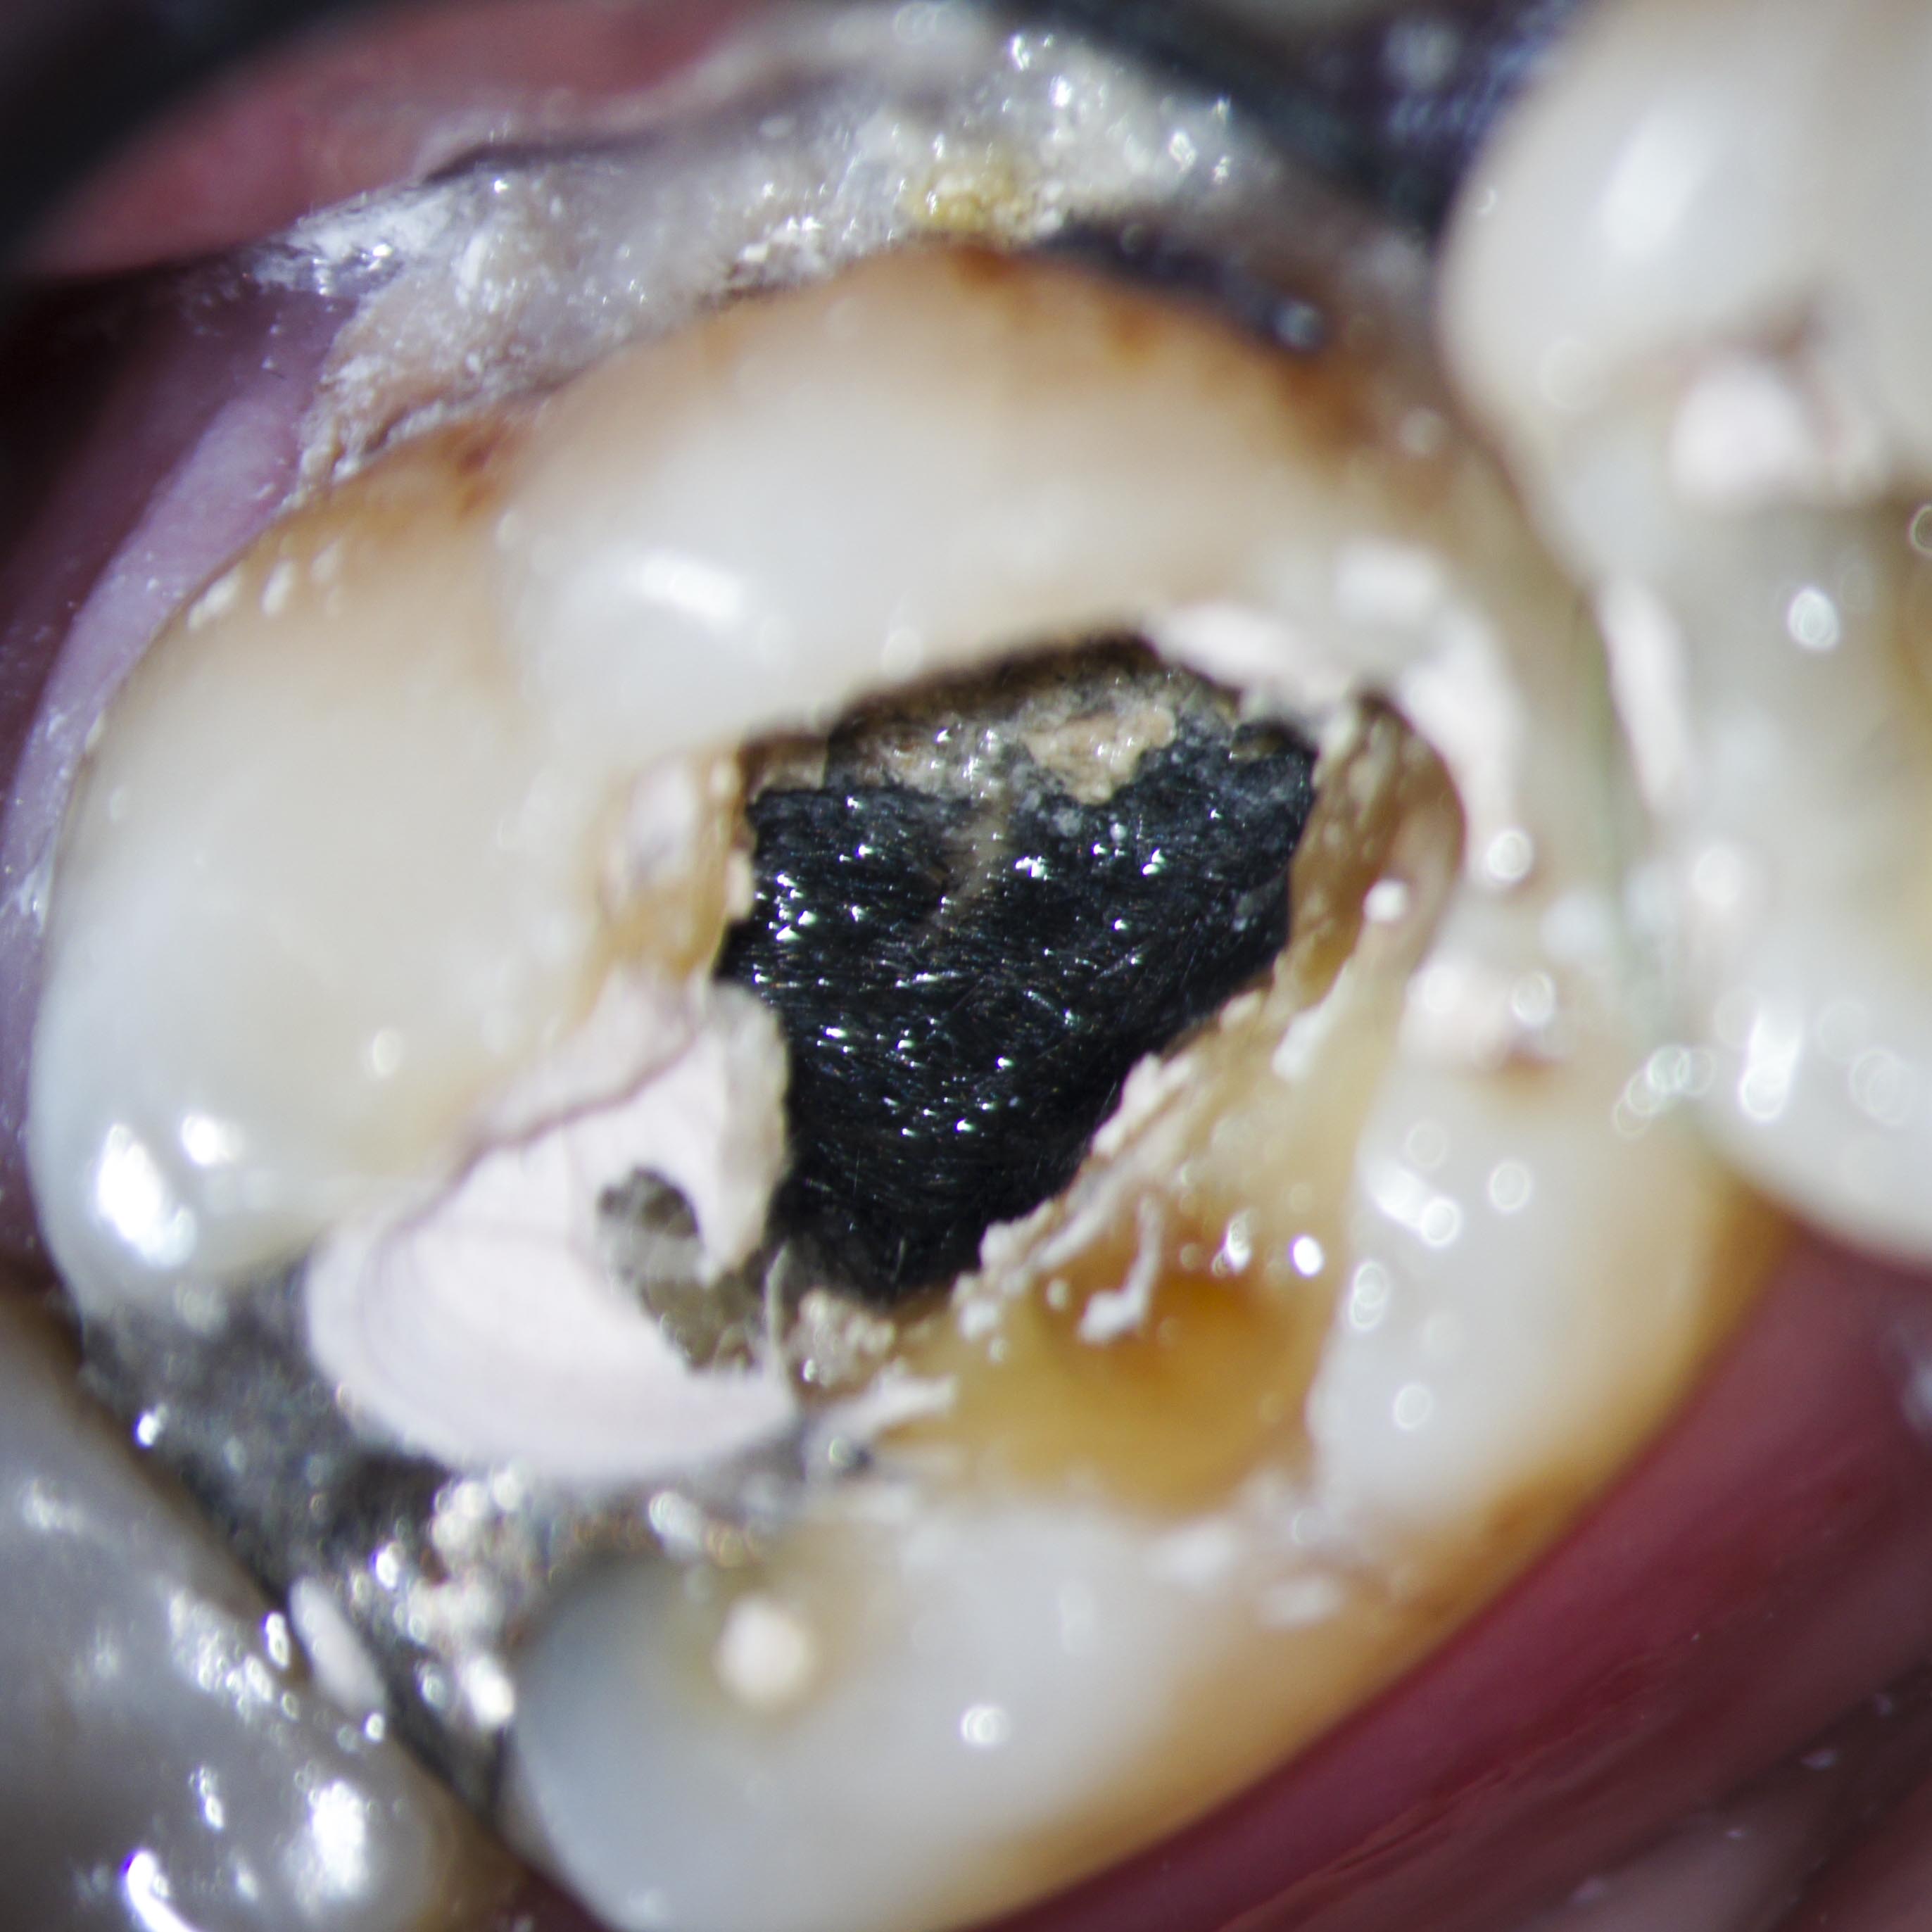

Gingivanekrose nach medikamentöser Einlage